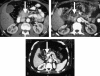

Results: The postoperative period was uneventful in all the patients, without complications or evidence of pancreatitis. The post RFA CT scan showed remarkable changes in the density and the characteristics of the tumors in all the patients. All the patients are alive, at 12, 8, 5 and 3 months postoperatively, respectively. In one patient (with cancer of the body of the pancreas) who was receiving morphine because of intolerable pain, significant pain relief has been observed.